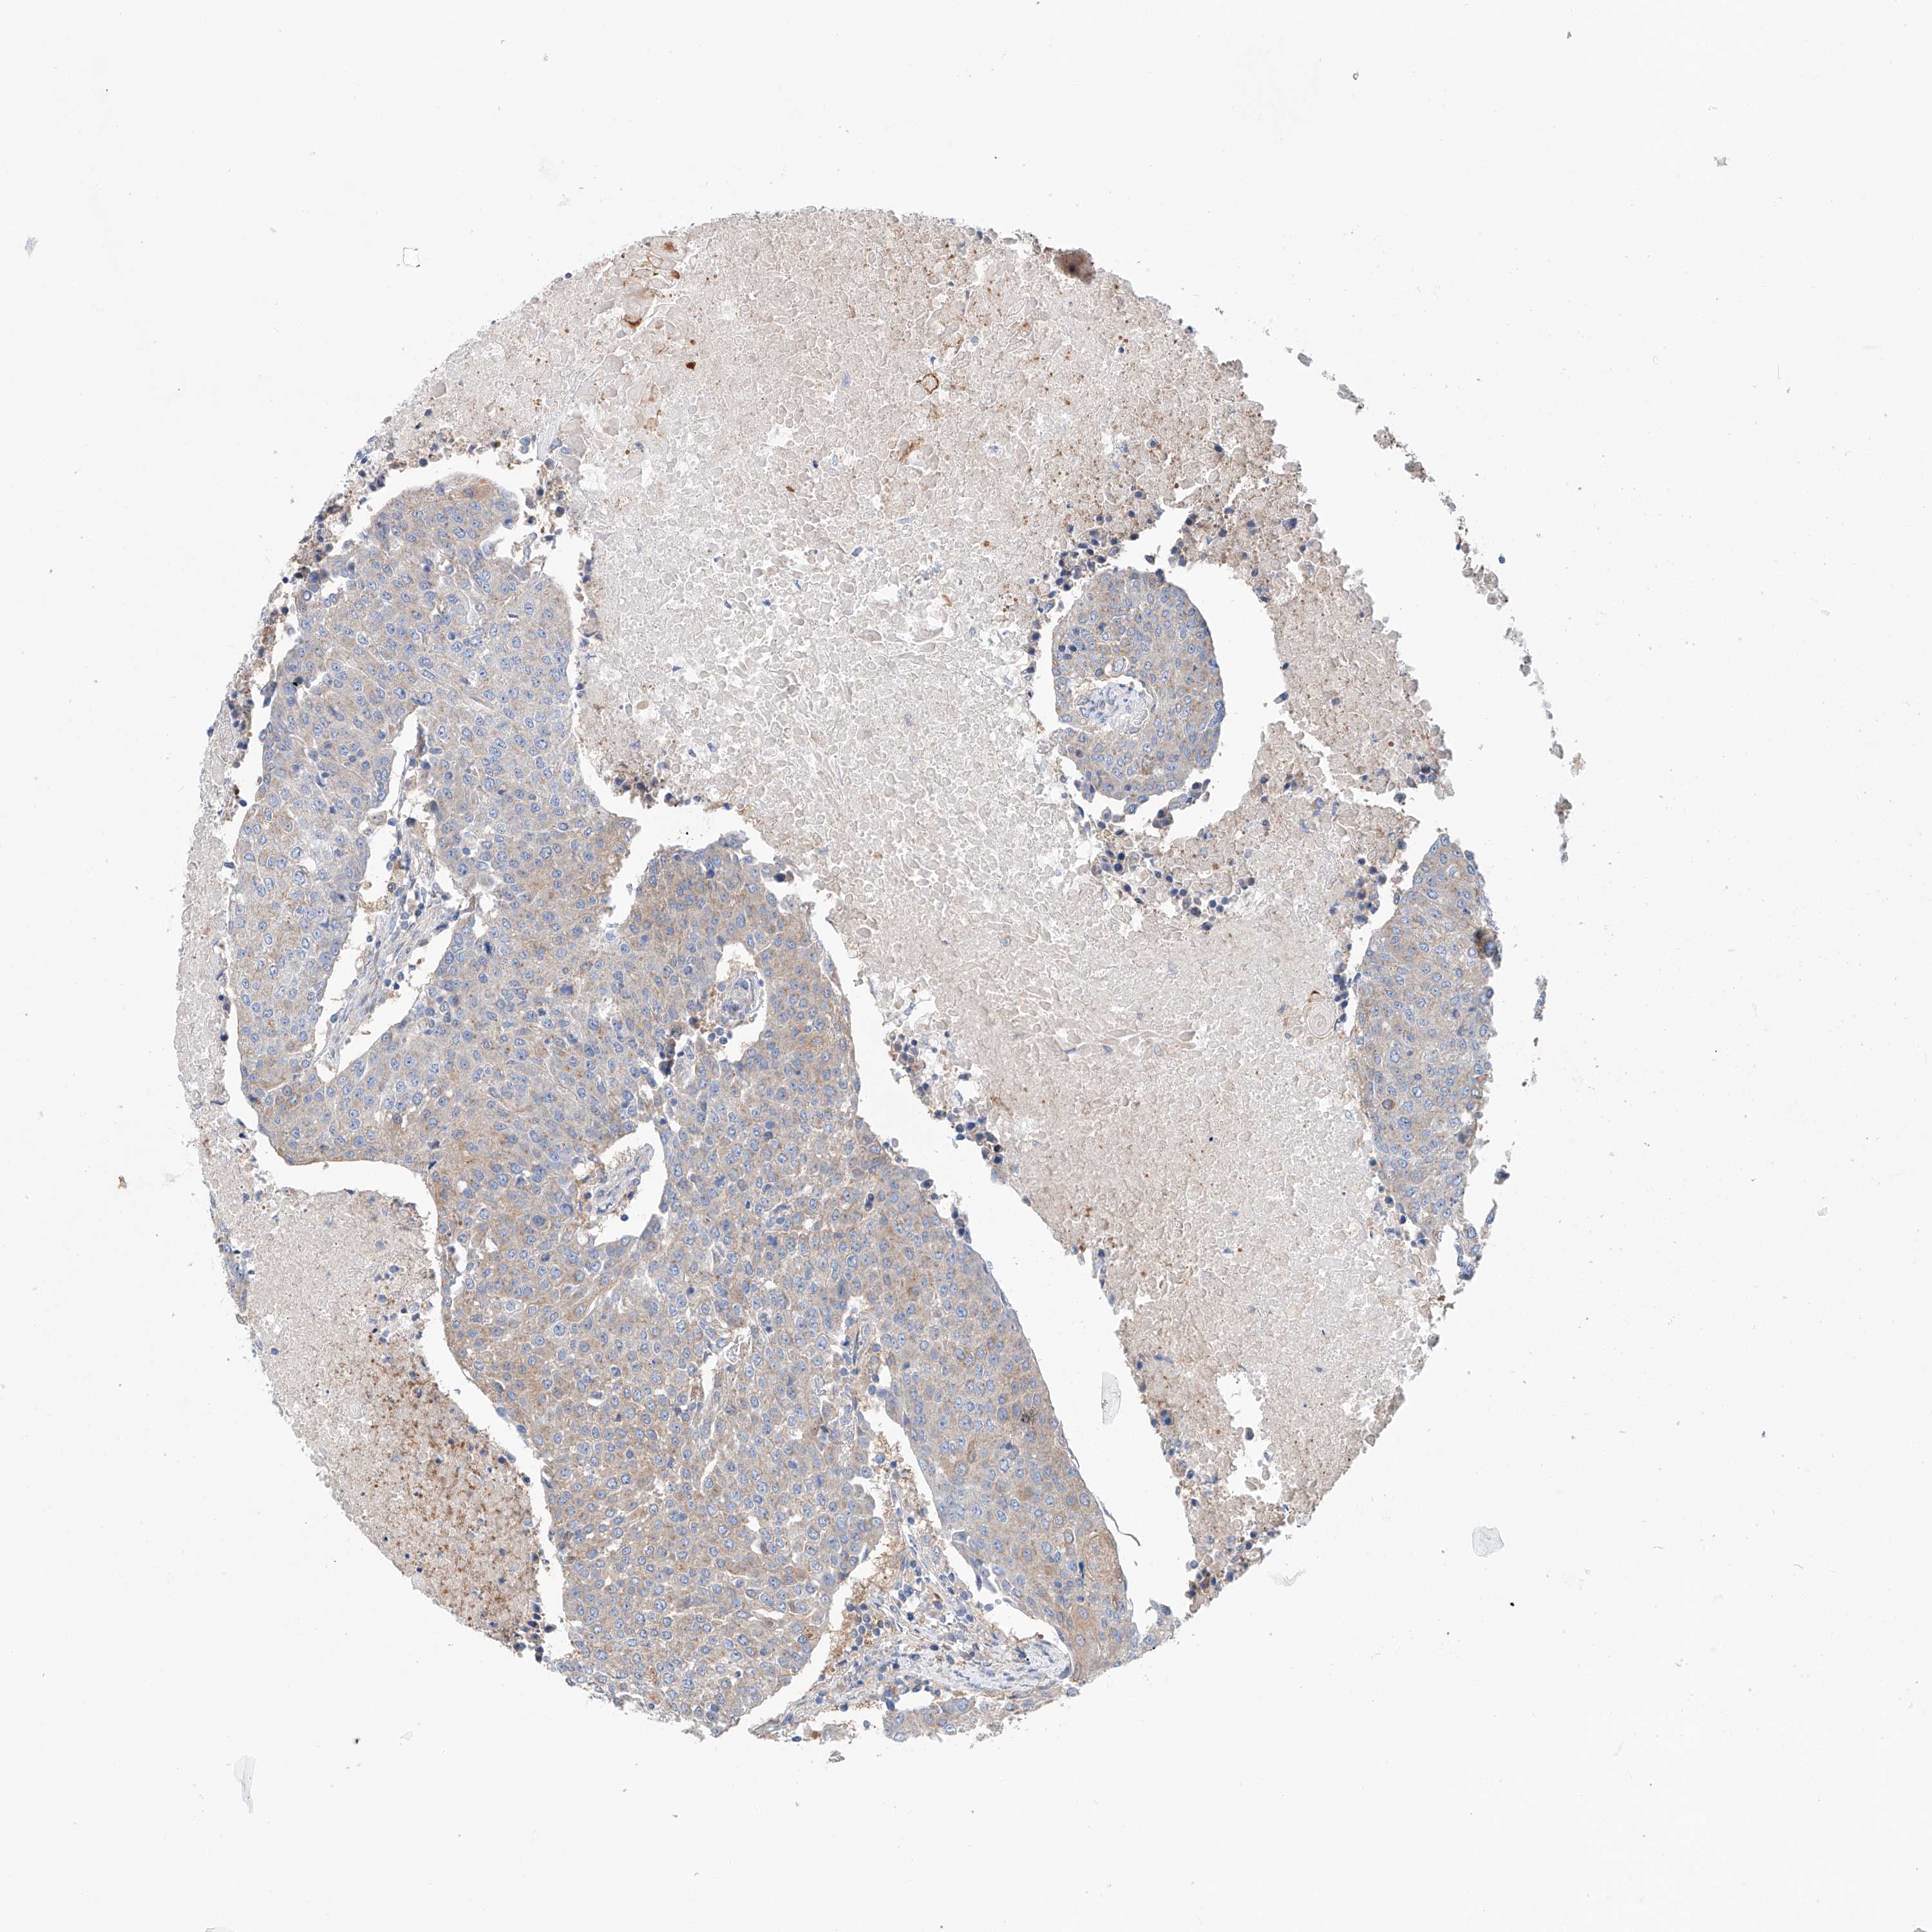

UROTHELIAL CANCER - Protein expressioni

A mouse-over function shows sample information and annotation data. Click on an image to view it in a full screen mode. Samples can be filtered based on level of antibody staining by selecting one or several of the following categories: high, medium, low and not detected. The assay and annotation is described here.

Note that samples used for immunohistochemistry by the Human Protein Atlas do not correspond to samples in the TCGA dataset.

Antibody stainingi

Antibody staining in the annotated cell types in the current human tissue is reported as not detected, low, medium, or high, based on conventional immunohistochemistry profiling in selected tissues. This score is based on the combination of the staining intensity and fraction of stained cells.

Each image is clickable and will lead to virtual microscopy that enables deeper exploration of all samples and also displays staining intensity scores, fraction scores and subcellular localization as well as patient and tissue information for each sample.

Antibody HPA030220

Staining

High

Medium

Low

Not detected

Intensity

Strong

Moderate

Weak

Negative

Quantity

>75%

75%-25%

<25%

None

Location

Nuclear

Cytoplasmic/membranous

Cytoplasmic/membranous,nuclear

Urothelial carcinoma, Low grade

Urothelial carcinoma, High grade